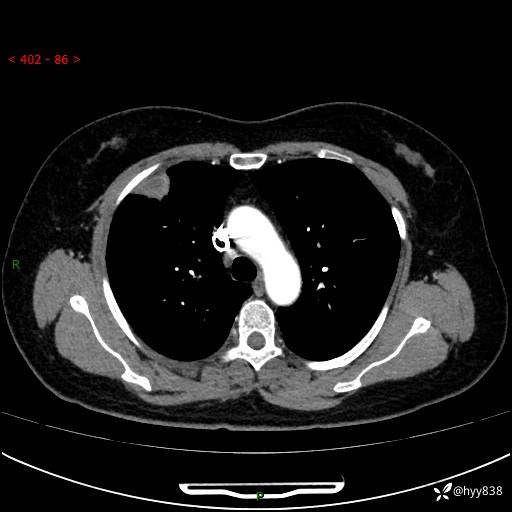

现病史:患者于2天余前无明显出现间断胸痛,无头痛、头晕,无心慌、胸闷、胸痛、呼吸困难、低热、盗汗,无腹痛、腹胀等不适,未进行进一步诊治。于2024.04.14在当地市人民医院行胸部CT检查提示:右肺上叶胸膜下结节。现患者为求进一步诊治,来我院就诊。以“肺肿物”收入我科。 患者自起病以来,精神可,睡眠可,饮食可,大小便正常,体重无明显改变。

胸部CT增强(肺窗,外院平扫)